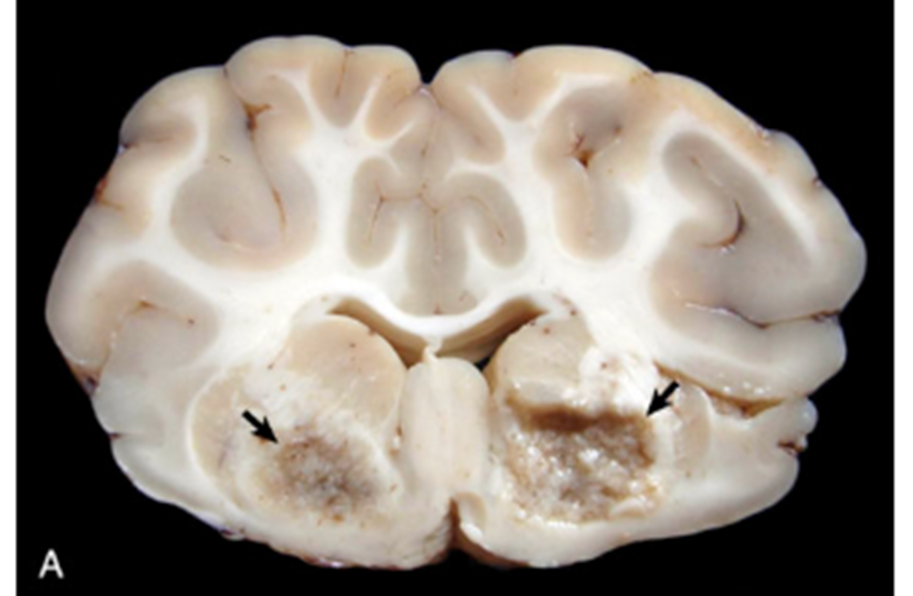

What pathology is shown in this image?

bilateral cerebrocortical lesions in a small ruminant indicating copper deficiency